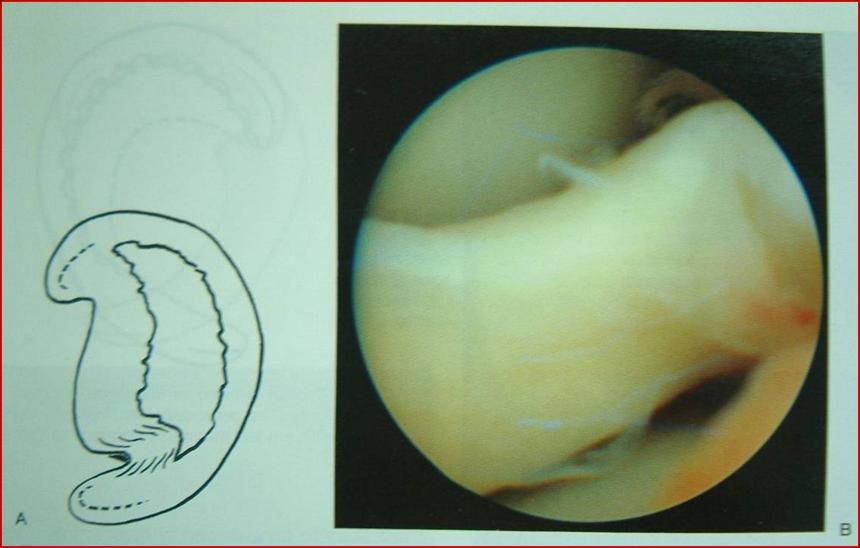

一:盤狀半月板

v原始型(完全型)

v中間型(不完全型)

v嬰兒型(接近正常,但體部鉸寬大)

盤狀半月板完全型

不完全型盤狀半月板

盤狀半月板的理解

vMRI上3個層面前后相連,還是存在半月板寬的。

v盤狀不一定是完全的,不完全的可能只是寬一點、厚一點,不一定非得邊緣很厚,只是較正常稍寬、邊緣微厚。